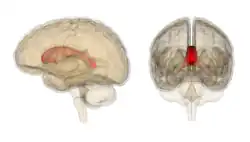

Corpus callosum from above, front part at the top of the image | |

Sagittal section of a brain, front part to the left. The corpus callosum can be seen in the center, in light gray | |

The corpus callosum (Latin for "tough body"), also callosal commissure, is a wide, thick nerve tract, consisting of a flat bundle of commissural fibers, beneath the cerebral cortex in the brain. The corpus callosum is only found in placental mammals.[1] It spans part of the longitudinal fissure, connecting the left and right cerebral hemispheres, enabling communication between them. It is the largest white matter structure in the human brain, about 10 cm (3.9 in) in length and consisting of 200–300 million axonal projections.[2][3]

A number of separate nerve tracts, classed as subregions of the corpus callosum, connect different parts of the hemispheres. The main ones are known as the genu, the rostrum, the trunk or body, and the splenium.[4]

The corpus callosum forms the floor of the longitudinal fissure that separates the two cerebral hemispheres. Part of the corpus callosum forms the roof of the lateral ventricles.[5]

The corpus callosum has four main parts – individual nerve tracts that connect different parts of the hemispheres. These are the rostrum, the genu, the trunk or body, and the splenium.[4] Fibres from the trunk and the splenium, known together as the tapetum ("carpet"), form the roof of each lateral ventricle.[6]

The front part of the corpus callosum, towards the frontal lobes, is called the genu ("knee"). The genu curves downward and backward in front of the septum pellucidum, diminishing greatly in thickness. The lower, much thinner part is the rostrum and is connected below with the lamina terminalis, which stretches from the interventricular foramina to the recess at the base of the optic stalk. The rostrum is named for its resemblance to a bird's beak.

The end part of the corpus callosum, towards the cerebellum, is called the splenium. This is the thickest part, and overlaps the tela choroidea of the third ventricle and the midbrain, and ends in a thick, convex, free border. Splenium translates as "bandage" in Greek.

The trunk of the corpus callosum lies between the splenium and the genu.